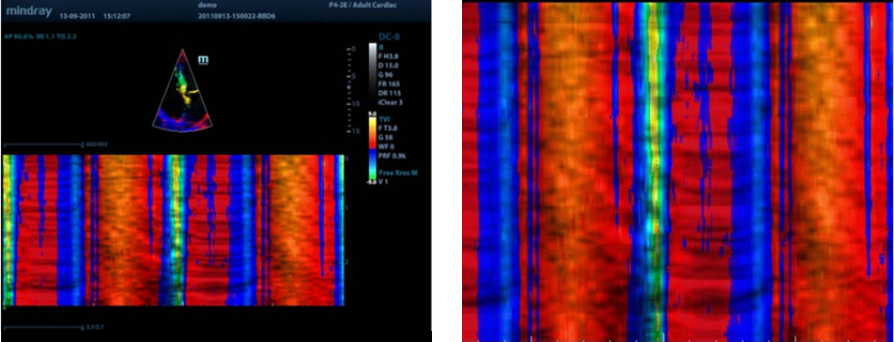

Free Xros CM?

Esatta valutazione del movimento miocardico in diverse fasi, con la possibilit├Ā di determinare allo stesso tempo la sincronizzazione miocardica. Alta frequenza di fotogrammi a garanzia di risultati precisissimi:

TDI

Le immagini doppler tissutali consentono di valutare quantitativamente il movimento e la funzione miocardica a livello locale, assicurando modalit├Ā TDI complete per diagnosi pi├╣ rapide e dirette.